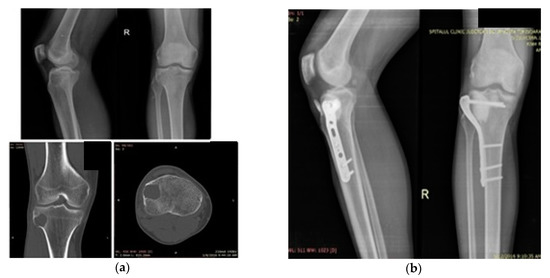

3.1. Case 1